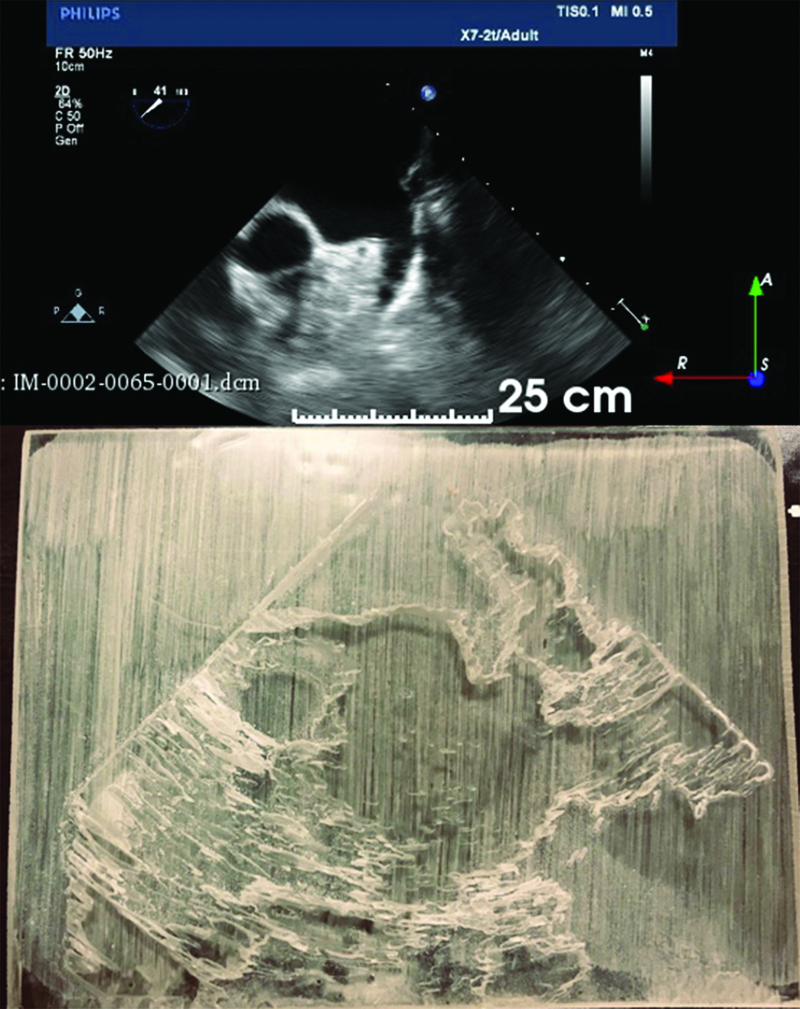

Figure 3

Figure 3. Top: TEE acquired image of left atrium. Bottom: 3D TEE printed model.